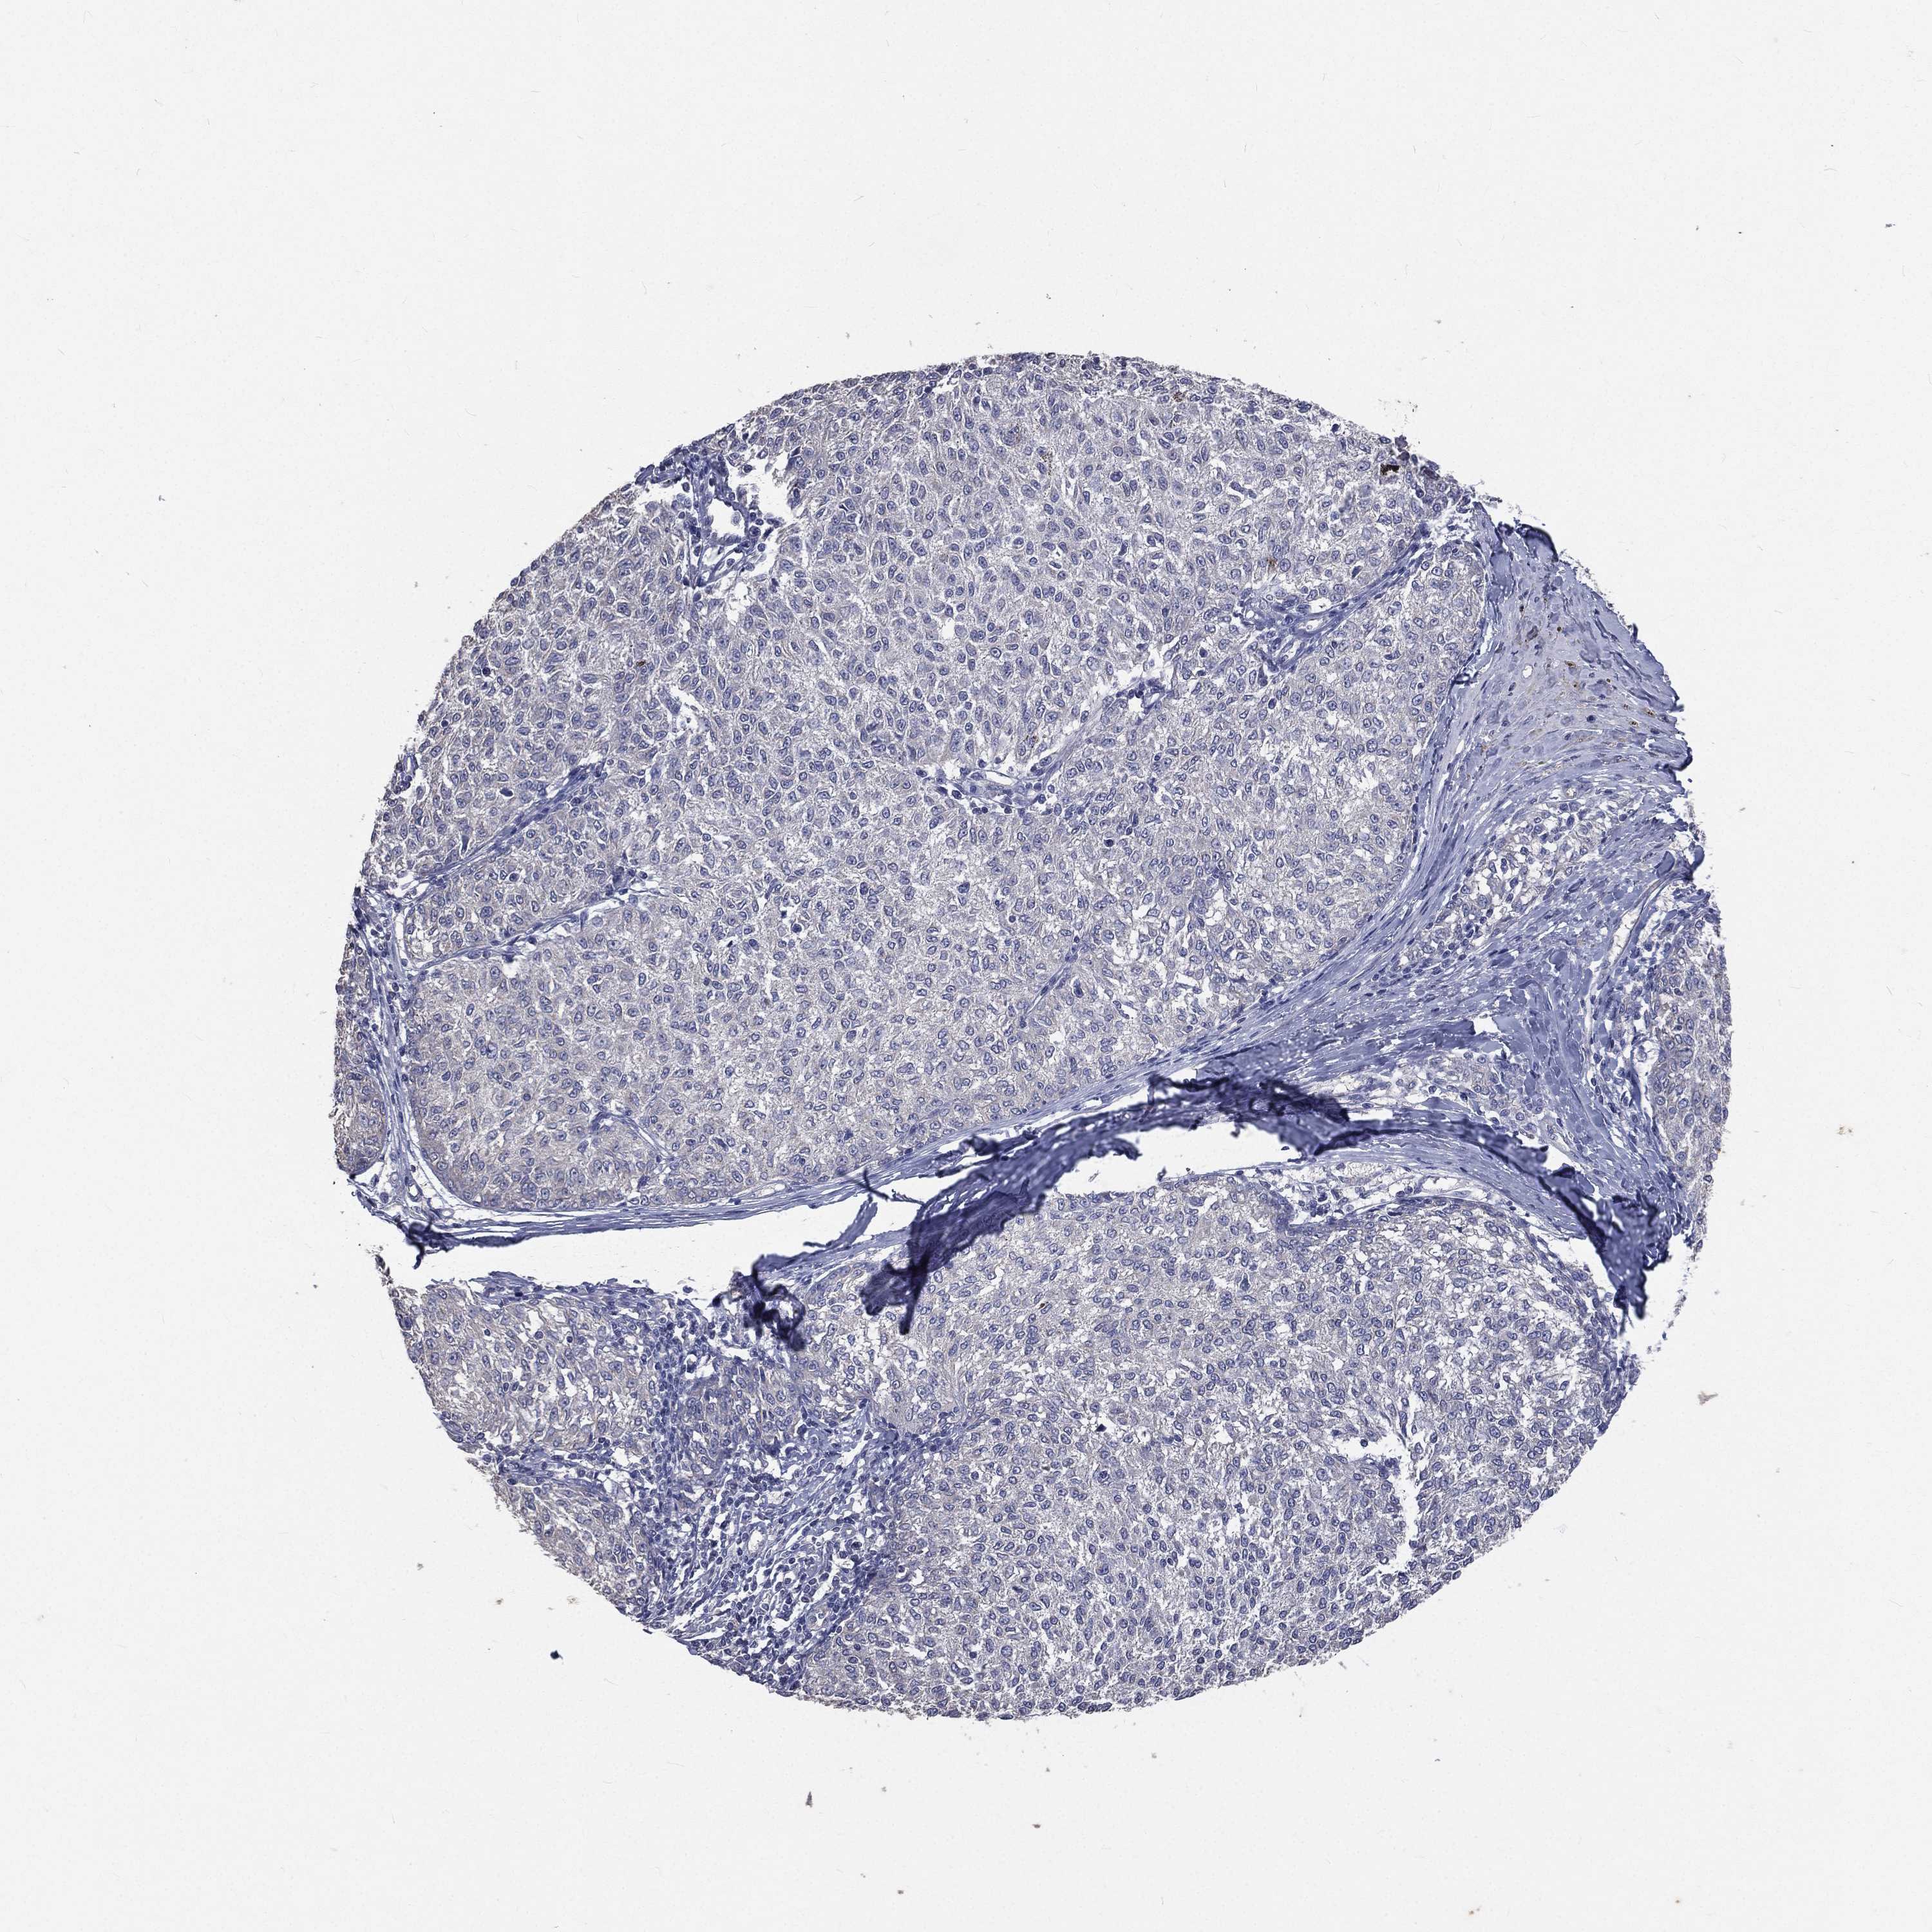

MELANOMA - Protein expressioni

A mouse-over function shows sample information and annotation data. Click on an image to view it in a full screen mode. Samples can be filtered based on level of antibody staining by selecting one or several of the following categories: high, medium, low and not detected. The assay and annotation is described here.

Note that samples used for immunohistochemistry by the Human Protein Atlas do not correspond to samples in the TCGA dataset.

Antibody stainingi

Antibody staining in the annotated cell types in the current human tissue is reported as not detected, low, medium, or high, based on conventional immunohistochemistry profiling in selected tissues. This score is based on the combination of the staining intensity and fraction of stained cells.

Each image is clickable and will lead to virtual microscopy that enables deeper exploration of all samples and also displays staining intensity scores, fraction scores and subcellular localization as well as patient and tissue information for each sample.

Antibody HPA021191

Antibody HPA021762

Malignant melanoma, NOS

Malignant melanoma, Metastatic site